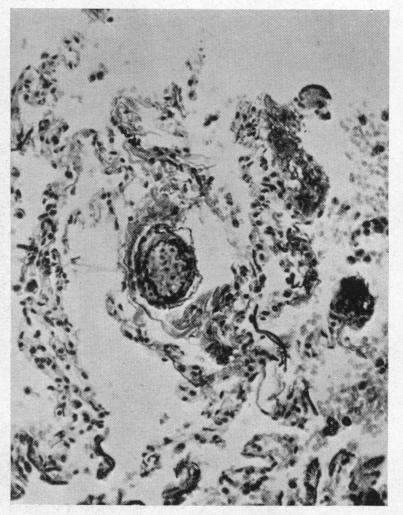

Eisenmenger's complex.

Br Heart J. 1955 Jul;17(3):273-84. doi: 10.1136/hrt.17.3.273.

Pulmonary vascular changes in Eisenmenger's complex.

J Pathol Bacteriol. 1959 Jan;77(1):141-7. doi: 10.1002/path.1700770115.